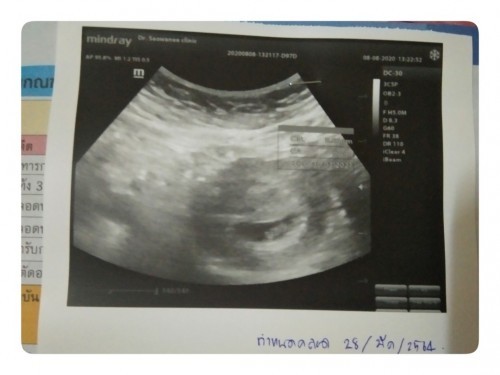

โพสต์อาจจะยาวหน่อยนะคะ แต่อาจจะเป็นกรณีศึกษาสำหรับใครหลายๆคนได้ค่ะ . จากโพสต์ที่แล้ว ที่ได้สอบถามหลายๆคนเรื่องเลือดที่ออกมา..จนในที่สุดก็ได้ไปพบแพทย์ในเย็นวันเดียวกันเลยค่ะ คุณหมอบอกว่าอาจเกิดจากการฝังตัว หรืออาจจะเป็นภาวะแท้งคุกคาม คุณหมอเลยให้ยากันแท้งมาทาน และนัดซาวด์ 11/8 พร้อมให้งดเดินเยอะ ยกของหนัก พสพ. เดินทางไกล . หลังจากกินยา อาการเลือดออกก็ดีขึ้นเรื่อยๆ แต่บางอย่างก็ยังงดไม่ได้เต็มที่ เช่น ขับจยย.ไปทำงาน เดินเยอะ เดินทาง แต่ก้อพยายามทำให้น้อยที่สุด และดีขึ้นมาเรื่อยๆ จนไม่มีเลือดไปห้าวัน แต่สุดท้ายเช้า 7/8 ปรากฎว่ามีเลือดออกมาอีกค่ะ . และวันนี้ วันที่ 8/8 เลยไปพบคุณหมอก่อนนัดเลยค่ะ ประกอบกับยาหมดพอดี คุณหมอซาวด์ก่อนเลยค่ะ ตอนซาวด์ลุ้นมาก กลัวเจอแค่ถุงตั้งครรภ์ แต่ในที่สุด ก็เจอน้องค่ะ เห็นหัวใจน้องเต้น ได้ยินเสียงหัวใจน้องด้วยค่ะ น้ำตาซึมไปเลยค่ะ และคุณหมอก็ได้ฉีดยากันแท้ง และงดทุกสิ่งอย่างข้างต้นอย่างจริงจัง ให้ใบรับรองแพทย์เพื่อพักงาน 1 สัปดาห์เลยค่ะ และคุณหมอแจ้งว่า หลังจากนี้หลังจาก 1 สัปดาห์หากมีเลือดอีก ก้อให้มาพบอีกค่ะ . วันนี้วันแรกที่แม่ต้องพักอย่างจริงจัง เคลื่อนไหวให้น้อยที่สุด เป็นกำลังให้แม่ด้วยนะคะ . ขอบคุณที่สละเวลาอ่านค่ะ ❤